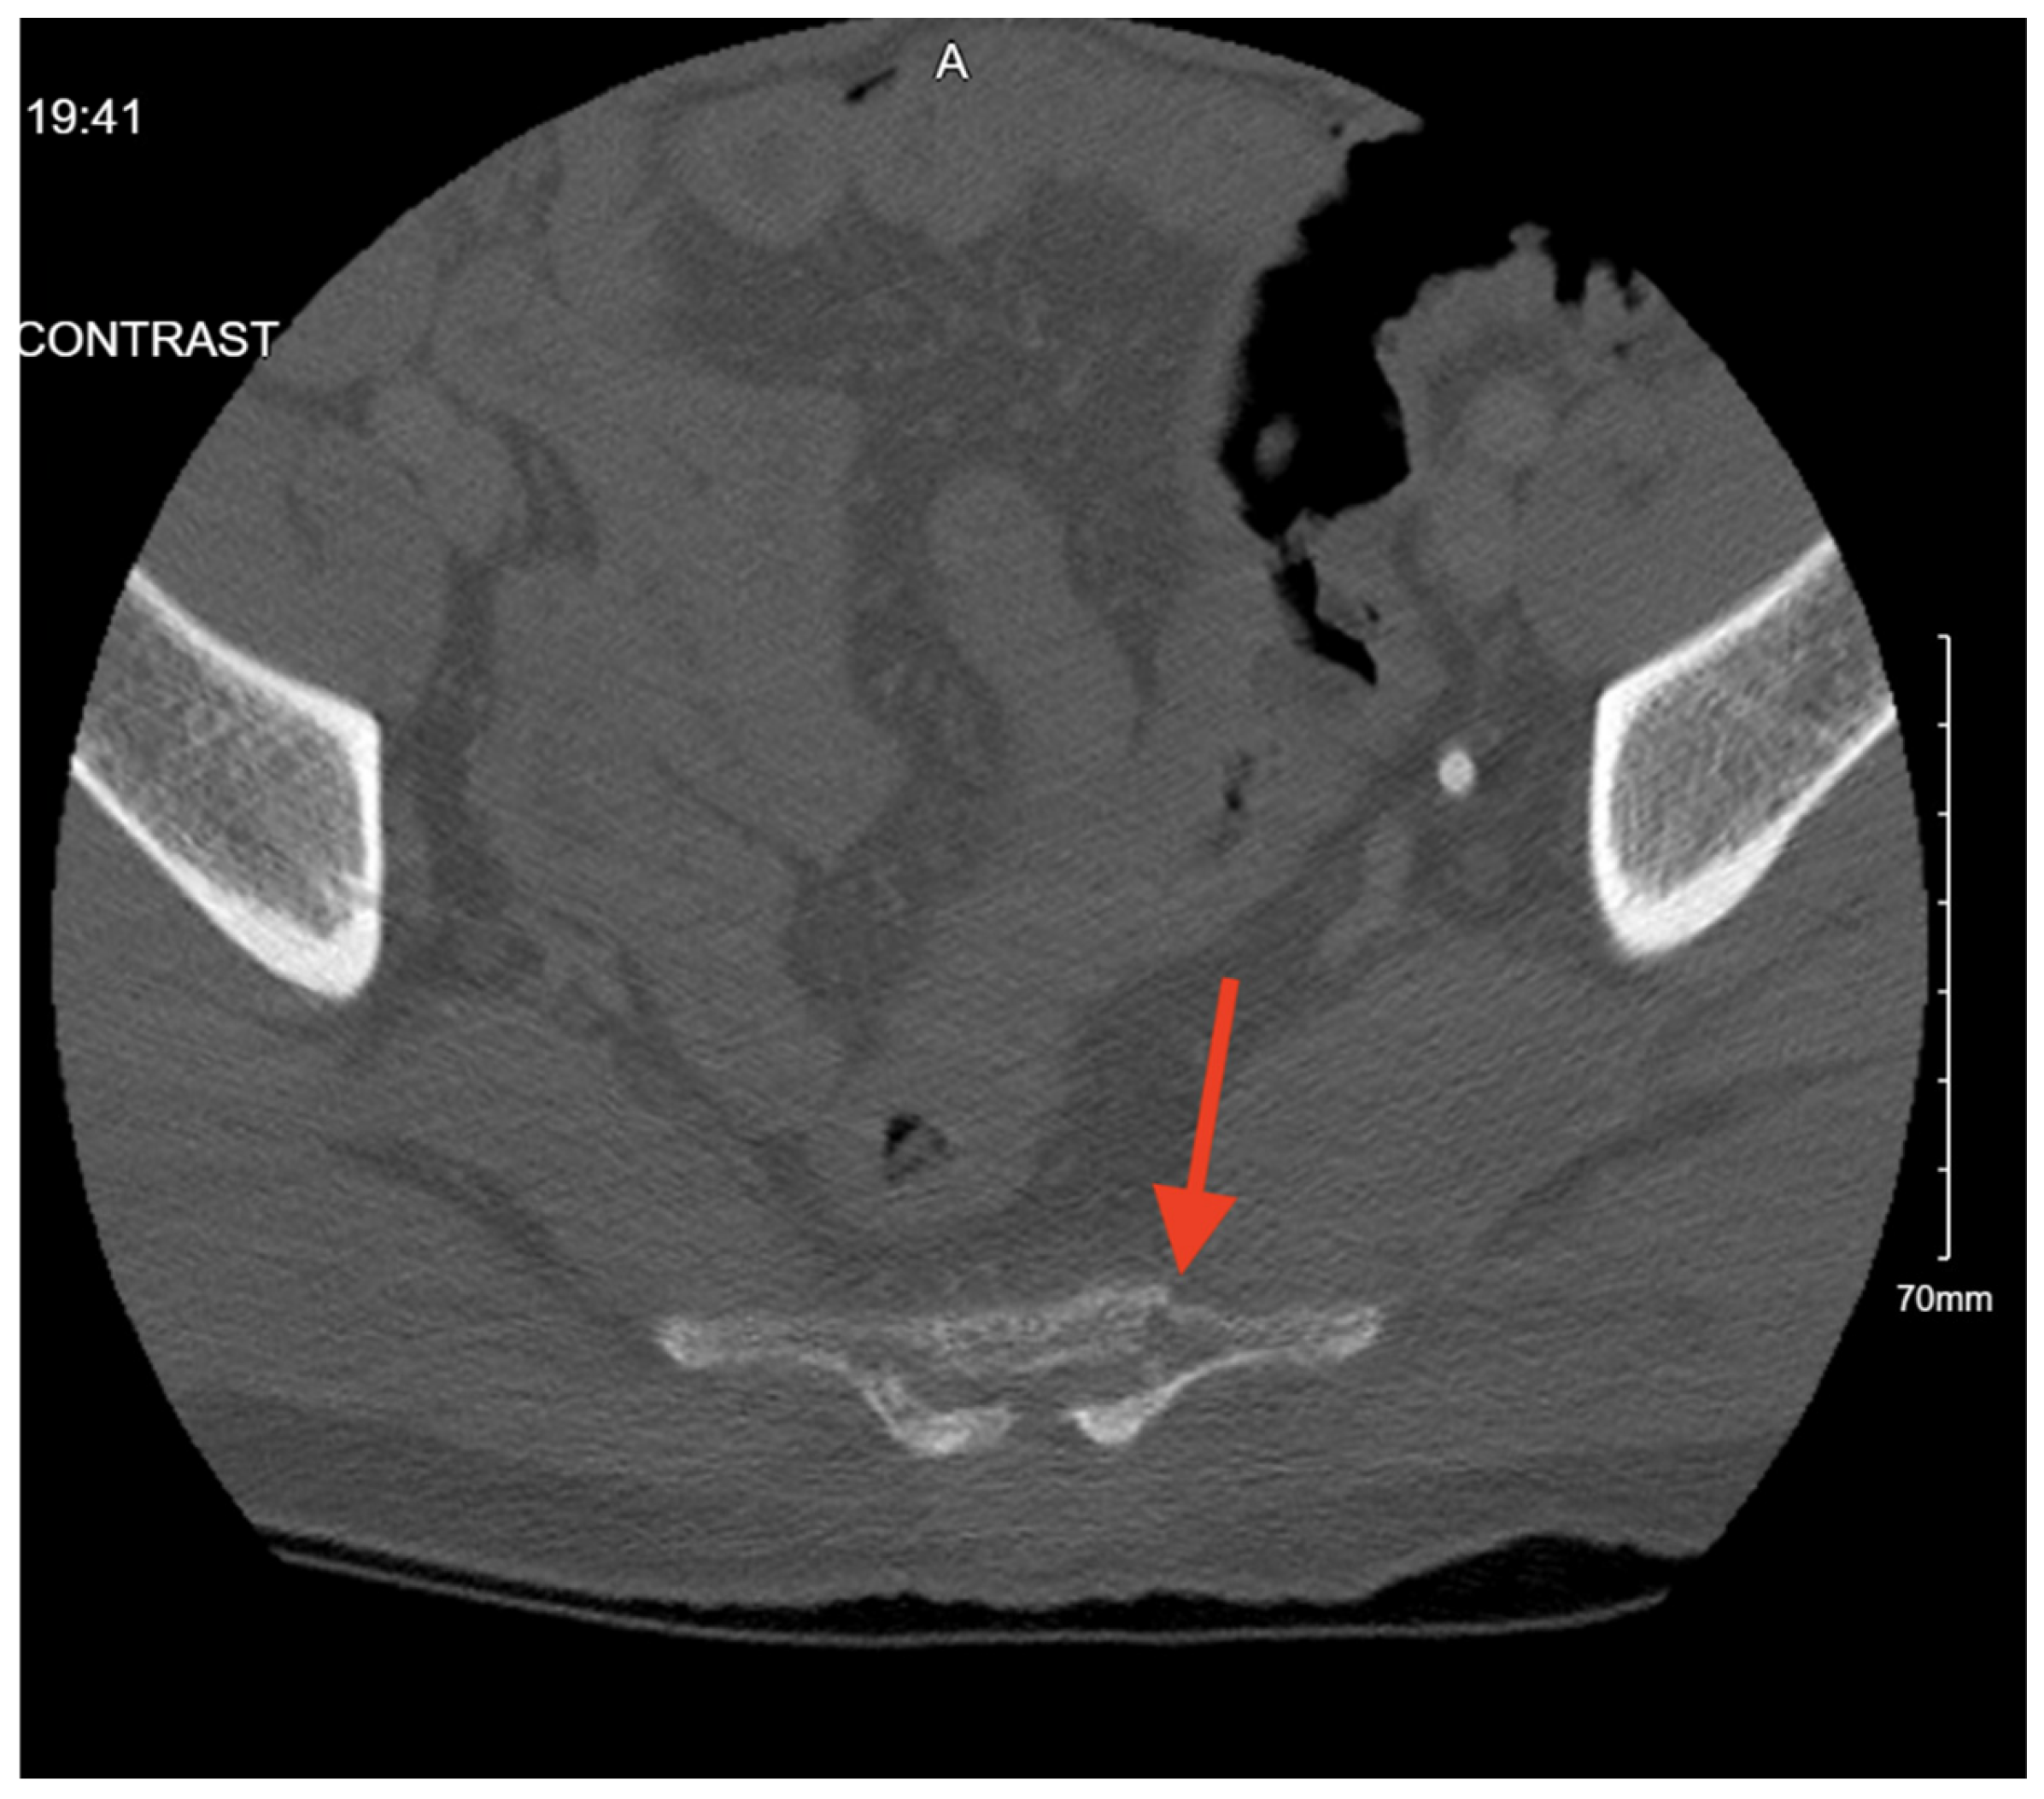

Pelvic imaging showed an acute impacted fracture involving the left superior and inferior pubic rami (Figure 2). She was also found to have diffuse asymmetric areas of subarachnoid blood throughout the frontal and parietal regions, with additional blood within the third and fourth ventricles and the posterior aspect of the occipital on CT head.

Figure 2. CT abdomen/pelvis images of the described fractures in case 2. Red arrows are used to indicate the location of pelvic fractures for easier identification.